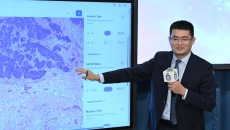

Trained on 500,000 pathology slides, the AI predicts cancer type, treatment response, and survival with over 95% accuracy within minutes.